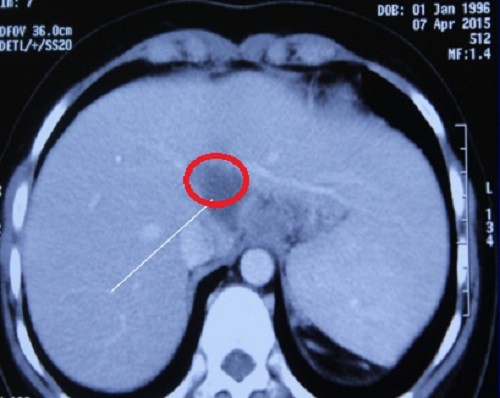

Hình ảnh lao gan được phát hiện ở nữ sinh

Trải qua 18 tháng sau điều trị, cơ thể nữ sinh được trở lại bình thường, kể cả kinh nguyệt. Nhưng khi siêu âm bụng kiểm tra định kỳ, các bác sĩ phát hiện một khối u ở gan đường kính 30mm. Kết quả sinh thiết gan cho thấy nữ sinh bị lao gan. Đây là căn bệnh hiếm gặp do gan là một tạng nghèo oxy, không thích hợp cho vi trùng lao phát triển. Lao gan chỉ thường xảy ra trên cơ địa suy giảm miễn dịch.